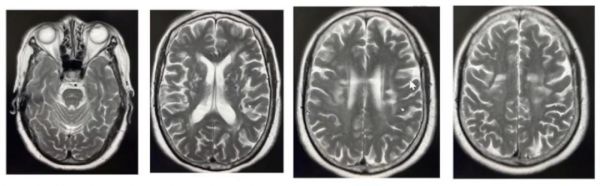

头颅MRI DWI(2022-02-21我院):左侧半卵圆中心腔隙性梗死(亚急性期)。

头颅MRI T2:脑桥、双侧脑室旁底节区和半卵圆区都有多发腔隙和小的缺血梗死灶。

头颅MRI FLAIR:底节区、半卵圆区、放射冠区都有多发的腔梗、缺血和白质高信号改变。

头颅MRA:颅内动脉硬化伴局限性狭窄。